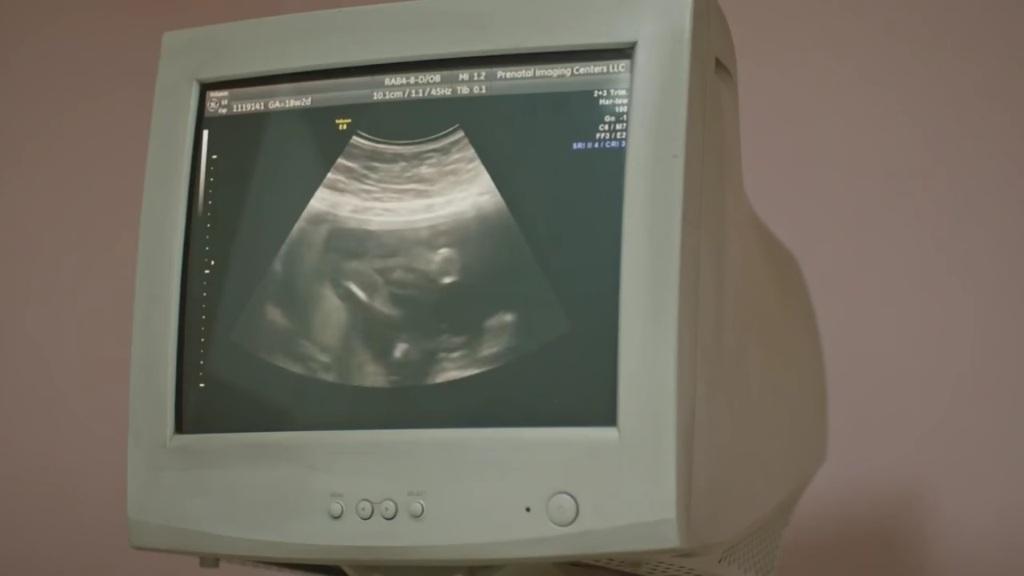

46 (piątek 9 lutego): Na farmę Cesura listonosz dostarcza list bez nadawcy. Okazuje się, że jest to kolejne pismo od Rizy! Mężczyzna udziela w nim rady: „Jesteś na dobrej drodze, nie myśl z niej schodzić”. Rano Cahide oraz Korhan mają problemy żołądkowe. Z listem od Rizy Cesur udaje się na policję. Adalet przed apteką także znajduje niepodpisaną kopertę. W środku jest list o treści „Obserwuję cię…”. Mihriban na leśnej ścieżce natrafia na wymiotującą Cahide. Zawozi ją do szpitala w Stambule. Na miejscu zjawia się także Korhan. Bulent wiezie Hulję do tego samego szpitala, by kolejny raz kobieta podała się za Cahidę. Przejeżdżająca obok Banu jest zaskoczona, kiedy widzi ich w jednym samochodzie. Bulent wraz z Hulją utknęli w korku i Cahide sama będzie musiała udać się na badanie USG! Jest przerażona wiedząc, że za chwilę runie jej misternie ułożony plan. Cesur otrzymuje wyniki ekspertyzy, zgodnie z którą w zwłokach jego ojca wykryto ślad po ranie postrzałowej. Mężczyzna jest teraz pewien, że jego ojciec został zamordowany. Doktor przeprowadza badanie USG Cahide. Nieoczekiwanie okazuje się, że kobieta naprawdę jest w ciąży! Kiedy wszyscy wychodzą, na salę wchodzi Hulja. Cahide okłamuje ją, że przekupiła lekarza i nie wyjawia prawdy, że jest w ciąży. Hulja zauważa jednak jej dziwne zachowanie. Suhan informuje Korhana o wynikach autopsji ojca Cesura.